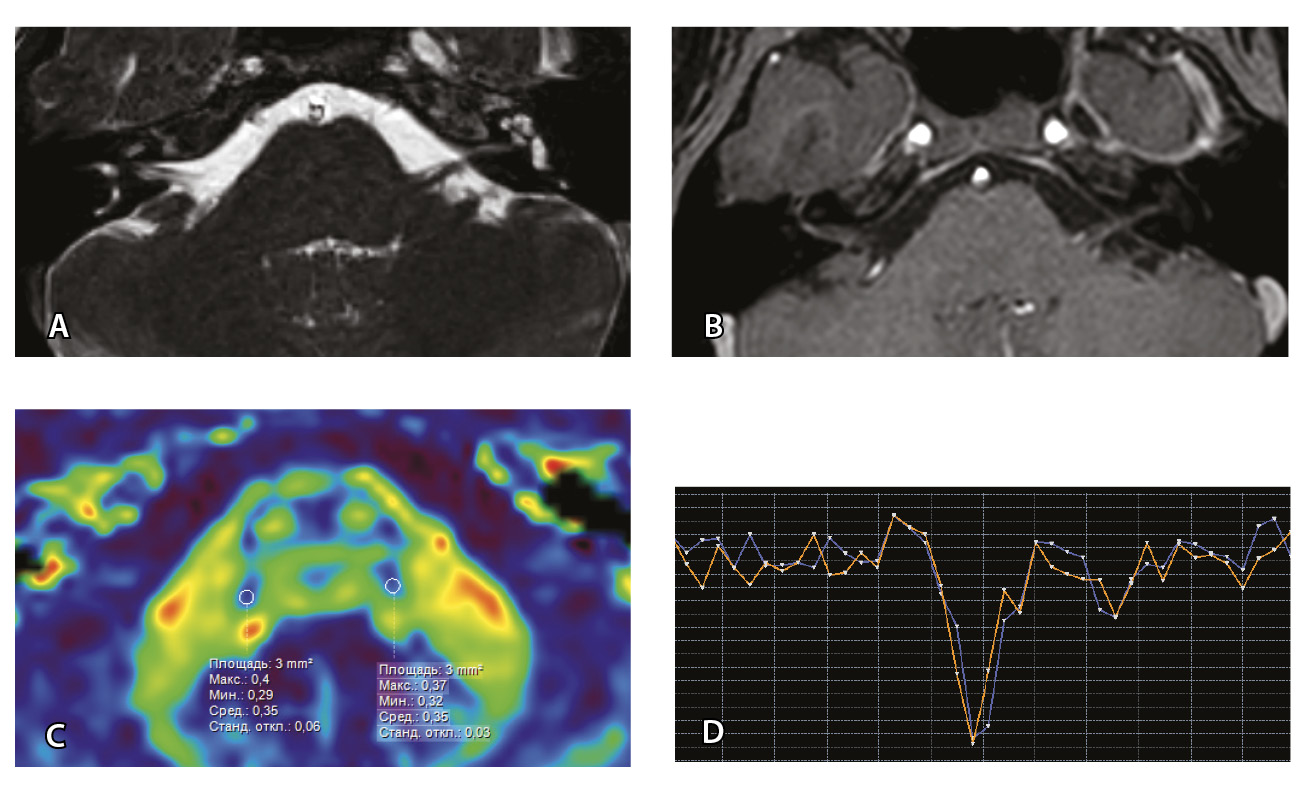

Рис. 3. Пациент Г. Магнитно-резонансная томография (МРТ) головного мозга: А – прицельная T2-SSFP на область мосто-мозжечкового угла; Б – Т1-взвешенное изображение с контрастным усилением; В – диффузионно-тензорная МРТ (фракционная анизотропия); Г – Т2*-перфузия (здесь и далее графики перфузии отражают зависимость повышения интенсивности МР-сигнала, то есть накопления контрастного вещества (вертикальная ось) от времени (горизонтальная ось), тем самым иллюстрируя основные показатели перфузии – relCBV, TTP, MTT). На изображениях T2-SSFP патологические изменения на уровне прохождения лицевых нервов во внутренних слуховых проходах (А), повышенное накопление вещества корешками лицевых нервов (Б) не определяются. Показатели фракционной анизотропии (В) и Т2*-перфузии (Г) на уровне моторных ядер лицевых нервов симметричны